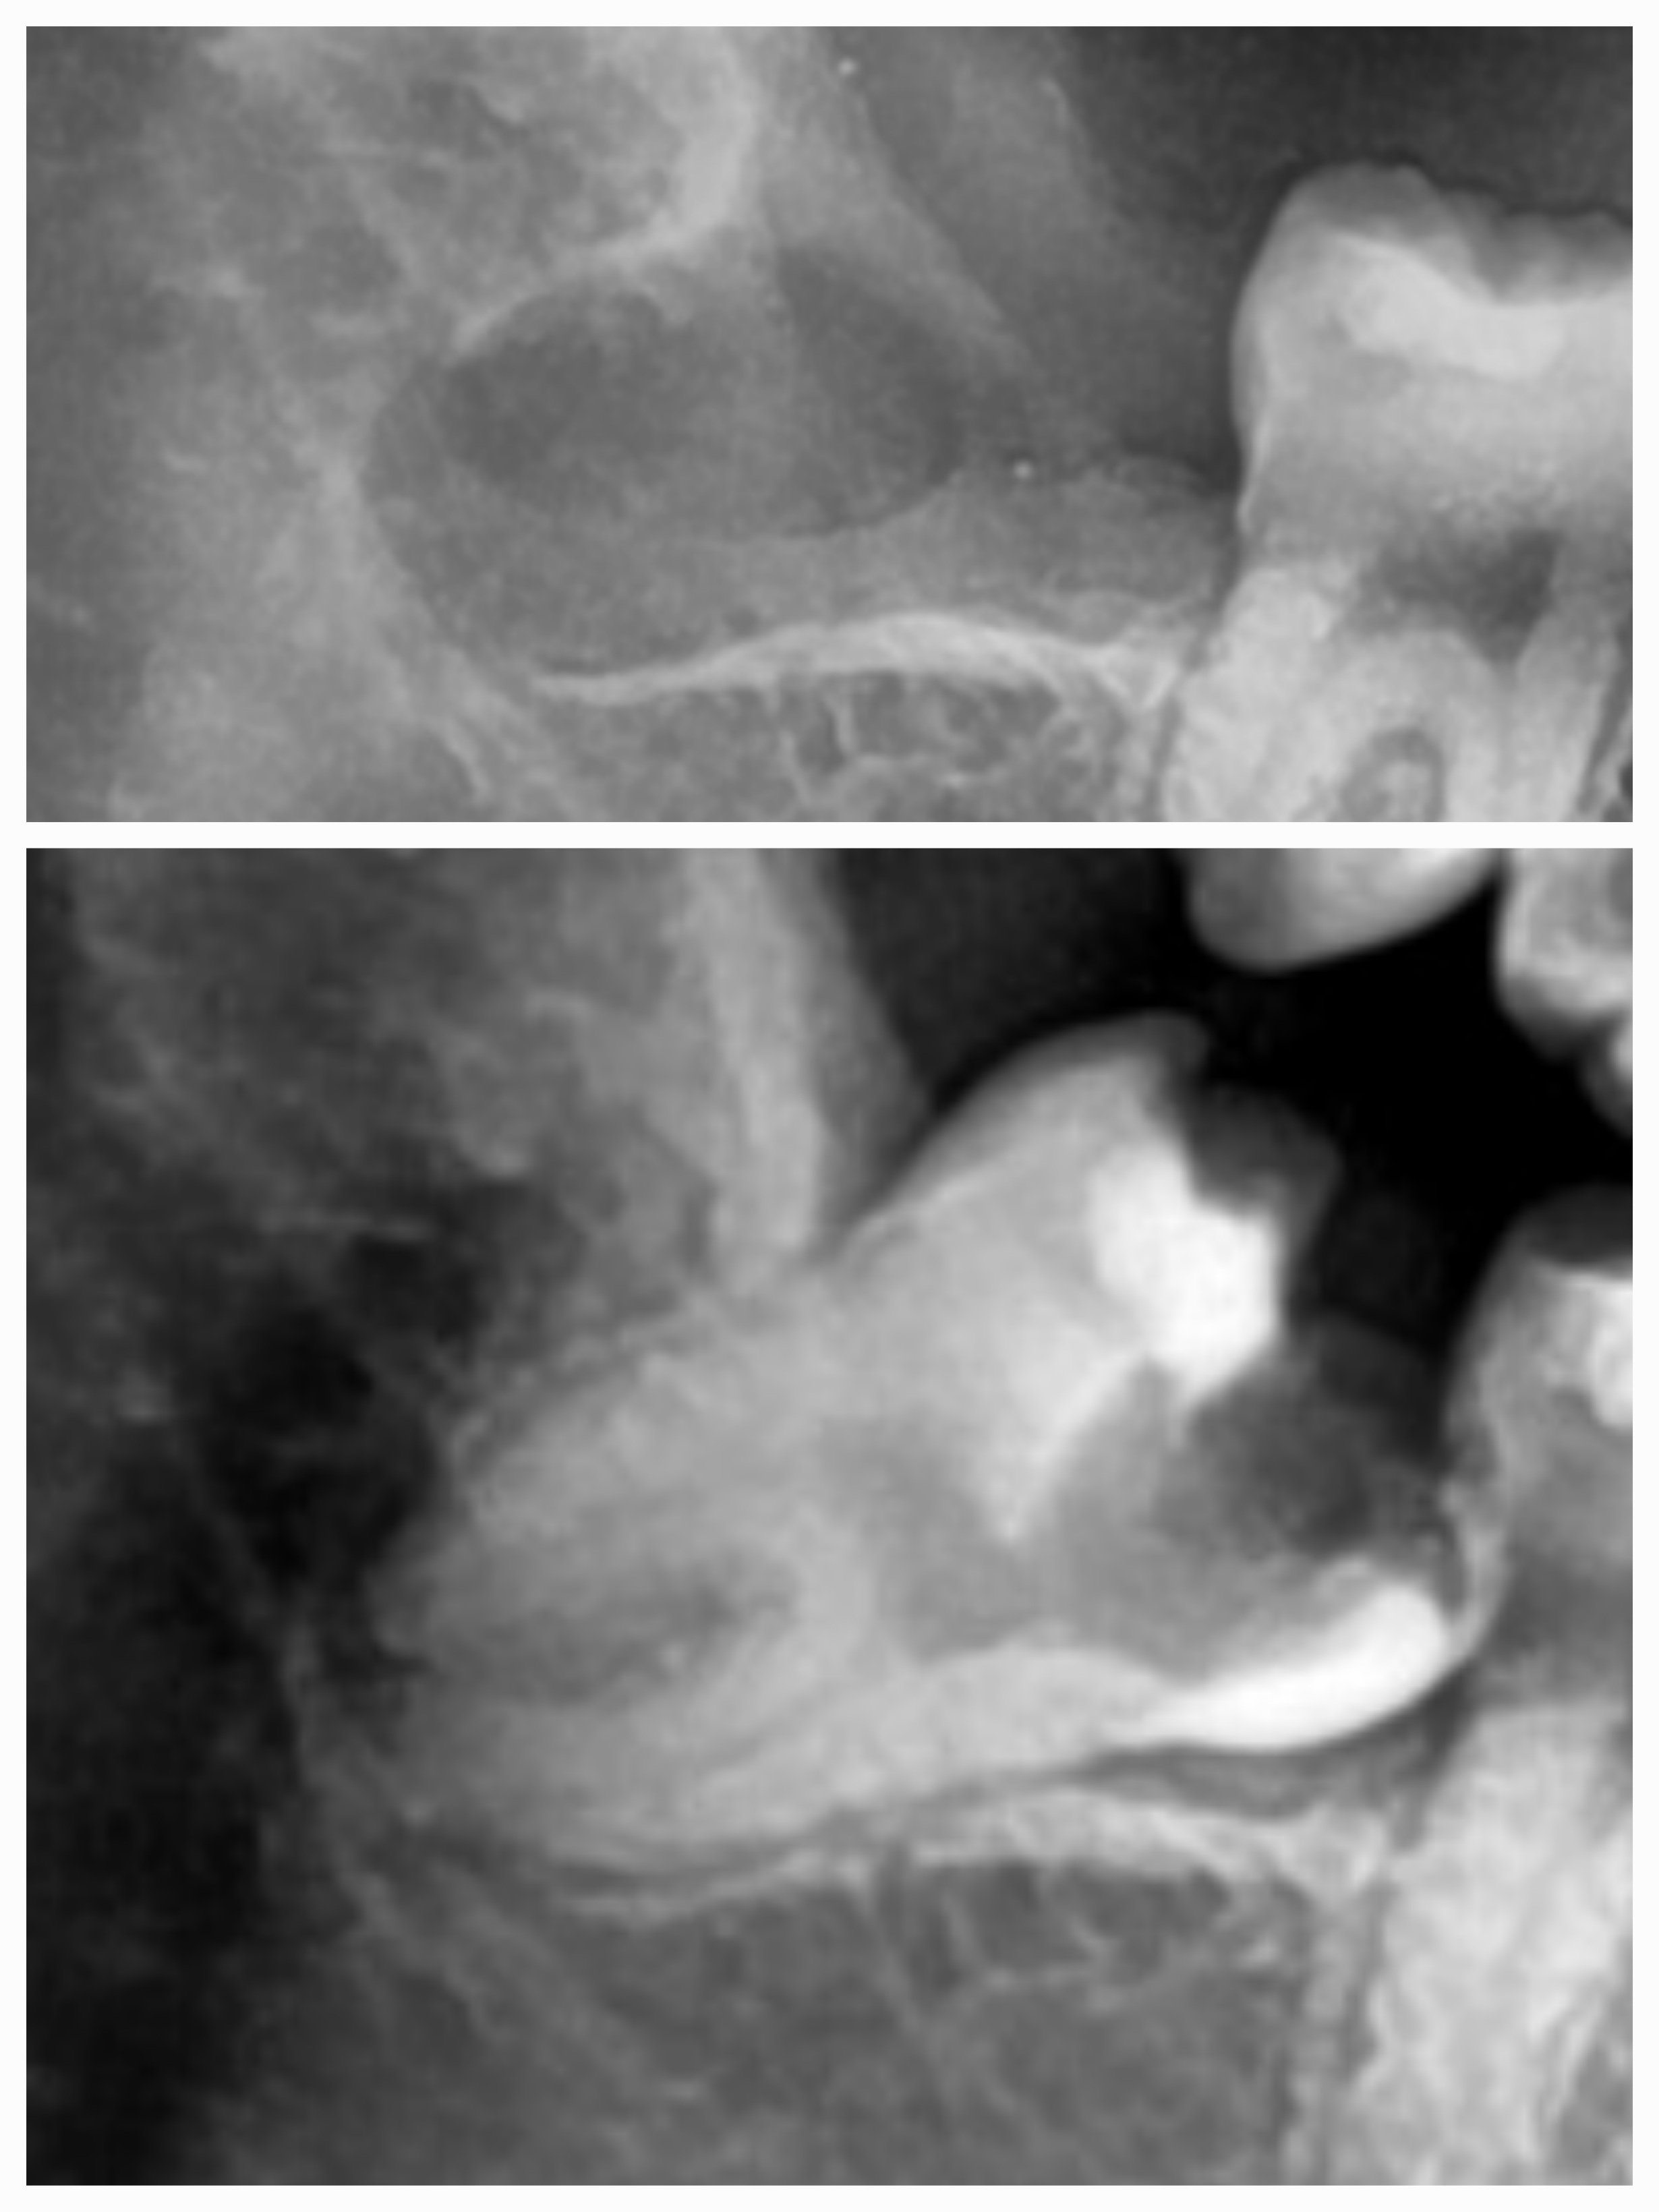

Severe decay. Tooth in 2 parts. Possible to save via hemisection.

Wisdom Tooth Class I Grade A and surgical removal of second molar.